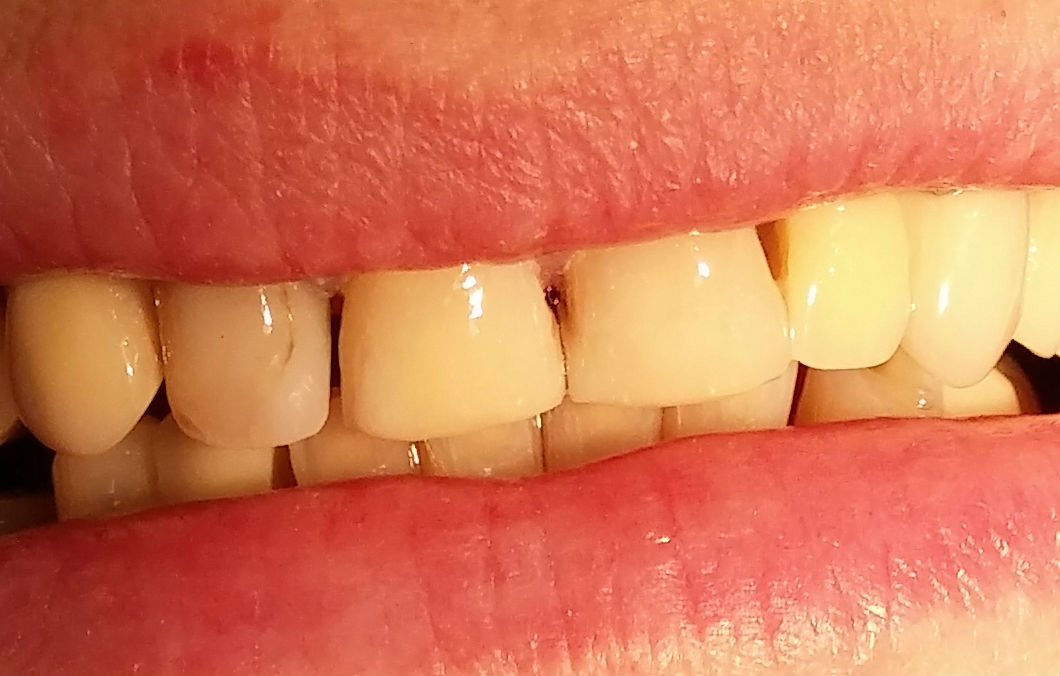

Konkurs sprawdzał umiejętności praktyczne studentów i dotyczył odbudowy zębów w odcinku przednim lub bocznym z użyciem materiałów stomatologicznych Dentsply Sirona.